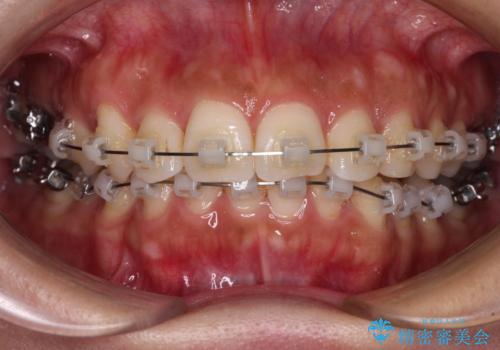

目立つ八重歯を改善 ワイヤー装置での抜歯矯正

- クリアブラケット

上顎の正中位置をほぼ保った状態で、綺麗に仕上げることができました。